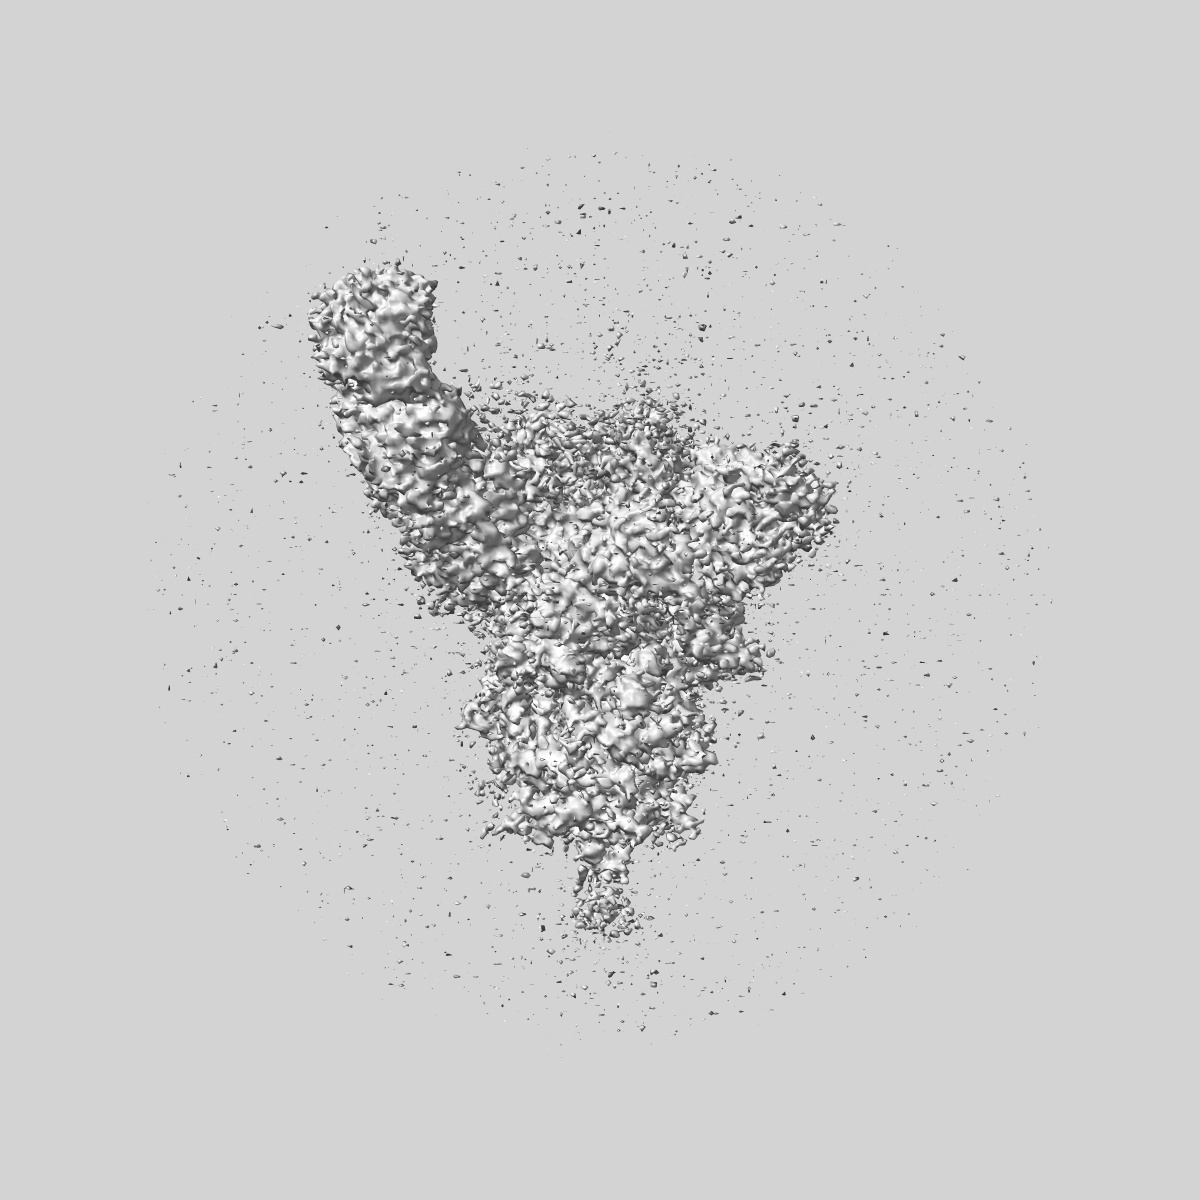

SARS-CoV-2 Wuhan Spike ectodomain in complex with human polyclonal antibody ModWu-NTD1 (mRNA-1273 vaccine)

Single-particle3.4 Å

Sample: SARS-CoV-2 Wuhan spike ectodomain in complex with human polyclonal antibody ModWu-NTD1